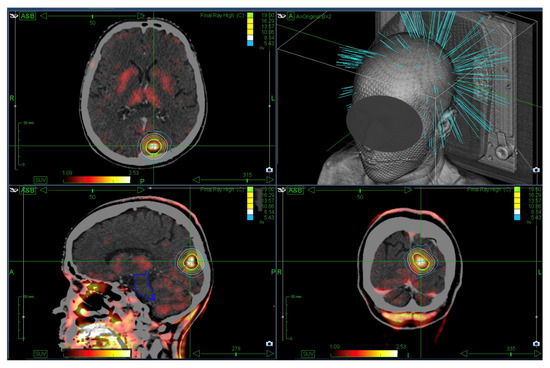

High-Dose Stereotactic Re-Irradiation of Recurrent High-Grade Gliomas: Clinical Outcome and Experience with AI-Based Target Volume Simulation

by Anton Früh, Franziska Loebel, Bohdan Bodnar, Larissa Kilian, Martin Misch, Goda Kalinauskaite, Anne Kluge, Chiara Eitner, Julia Onken, Kerstin Rubarth, Daniel Zips, Peter Vajkoczy, Carolin Senger and Güliz Acker

Background/Objectives: Despite multimodal therapeutic concepts, treatment of recurrent malignant gliomas remains challenging. Stereotactic radiosurgery (SRS) may be a possible safe and effective non-invasive salvage treatment. In this study, we aim to investigate the SRS treatment outcomes using partly 18F-Fluorethylthyrosine (FET)-PET-imaging sequences for SRS [...] Read more.

Background/Objectives: Despite multimodal therapeutic concepts, treatment of recurrent malignant gliomas remains challenging. Stereotactic radiosurgery (SRS) may be a possible safe and effective non-invasive salvage treatment. In this study, we aim to investigate the SRS treatment outcomes using partly 18F-Fluorethylthyrosine (FET)-PET-imaging sequences for SRS treatment planning focusing on overall survival, event-free survival, and the incidence and factors influencing radiation necrosis (RN) occurrence. Additionally, we evaluated the potential application of AI-based tumor segmentation. Methods: We conducted a retrospective analysis of patients with recurrent malignant glioma treated with single-fraction or hypofractionated SRS at our institution. The outcomes assessed included local control, overall survival (OS), and local event-free survival (LEFS, defined as the interval until tumor recurrence or the onset of RN). We also performed a simulation analysis to assess the potential of AI-based tumor segmentation. Results: The study included 27 patients with a median age of 57 years and 41 lesions. The median OS post-SRS was 9.6 months and an LEFS of 5.2 months. Factors positively influencing OS and LEFS included the gross tumor volume (GTV) of the lesions before SRS therapy, presence of an IDH mutation, and lomustine treatment post-SRS. The incidence of RN post-SRS was 31.7%. RN was confirmed histopathologically in 15.4%, based on MRI in 46.2% and by FET-PET in 38.5% of lesions. In a simulation analysis, AI-based tumor segmentation reliably delineated all lesions, requiring only minimal manual adjustments to define target volumes. Conclusions: High-dose SRS is a feasible salvage treatment for small-volume recurrent high-grade gliomas, achieving local control and survival outcomes comparable to other re-irradiation strategies. IDH mutation, smaller tumor volume, and lomustine therapy were associated with improved survival. RN occurred frequently, particularly in periventricular lesions. AI-based tumor segmentation showed promise in well-defined satellite recurrences, but remains limited in cavity-adjacent lesions, underlining the need for expert review and 18FET-PET imaging. Full article

Show Figures

Figure 1